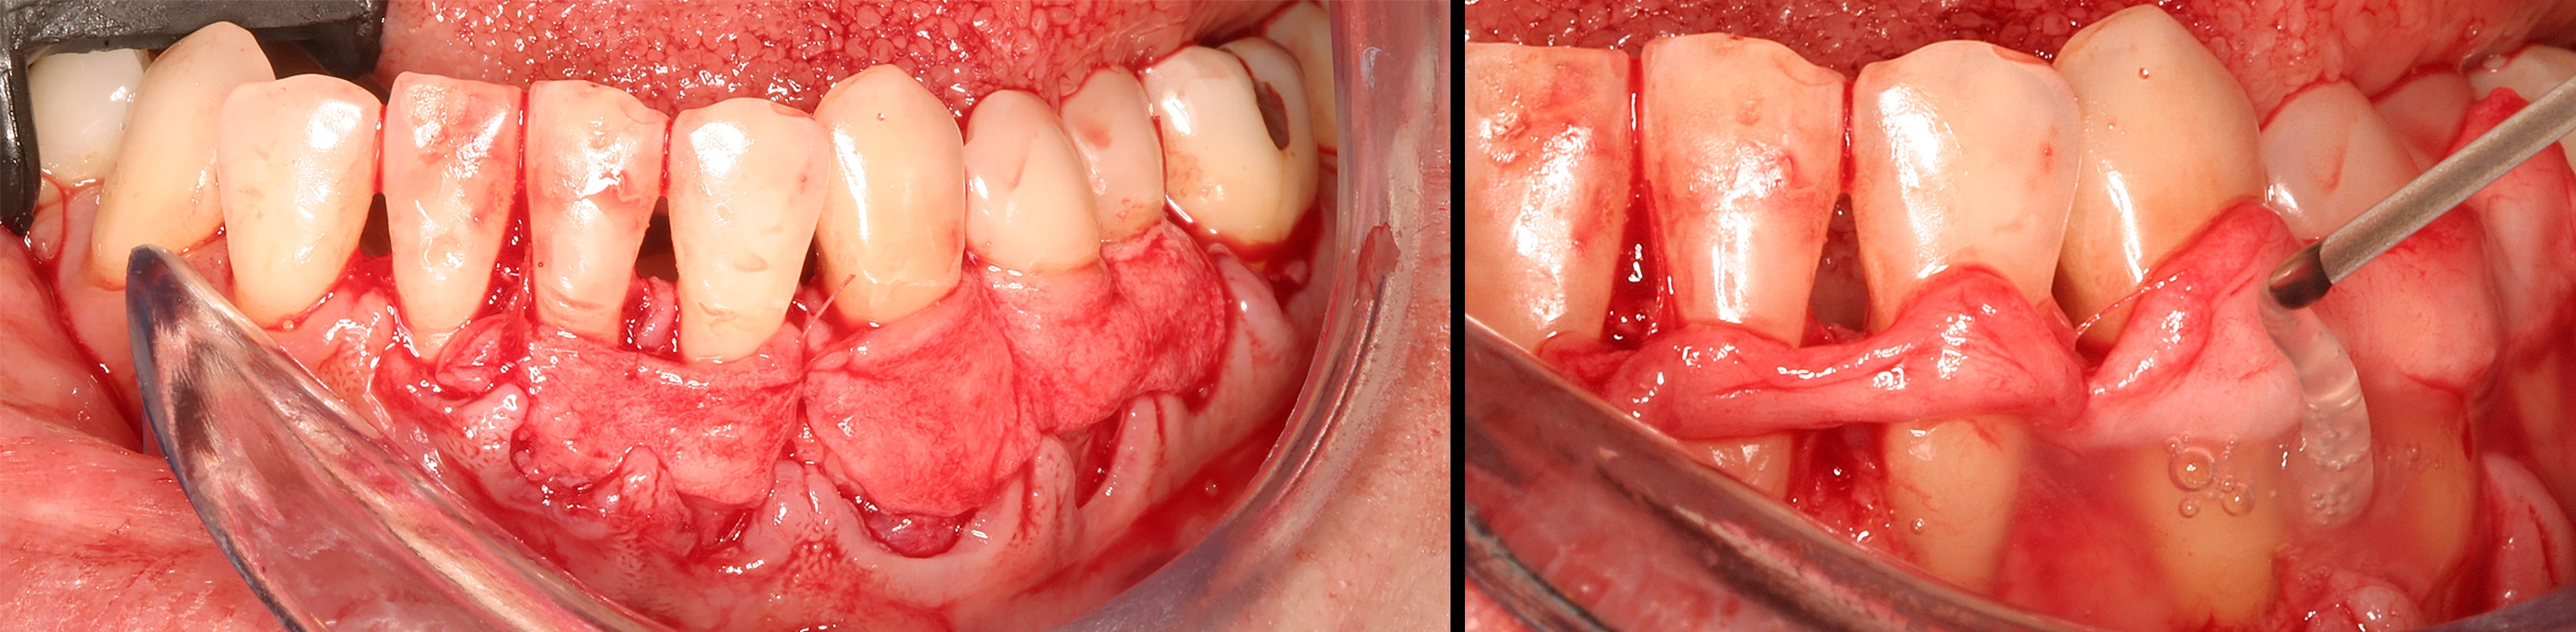

Preoperative recession.

Fig. 8

Acellular dermal graft combined with enamel matrix derivative.

Fig. 9

The 2.5-year postoperative photograph.

Fig. 10

In the coming decades, restorative treatment for aging patients who experience facial growth with recession and erosion below the cemento-enamel junction because of tooth movement may be especially challenging. However, if dentists can employ the tenets of regeneration using autogenous tissues or a cellular dermal matrix combined with enamel matrix derivatives as a regulatory protein, they may predictably achieve large amounts of root coverage with thickened periodontium. This would not eliminate the need for restorative dentistry, but would enable restorative dentists to place restorations that are supragingival and are easily accessible for the patient and the therapist during maintenance (Figure 8 through Figure 10).